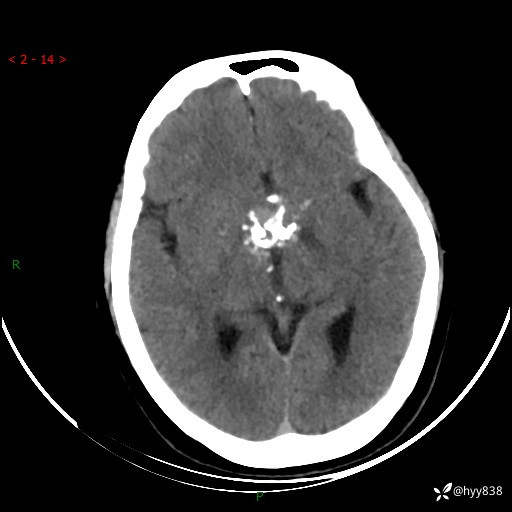

颅脑CT平扫

老年女性,视力下降3年。鞍区钙化性肿块,鉴别诊断有哪些---(有结果)

简要病史:患者3年前无明显诱因左眼出现视力下降,出现视物模糊,无头痛,无头晕,无恶心、呕吐,无意识障碍,无肢体麻木及抽搐,无心慌、胸闷,无腹痛、腹胀等不适,无旋地转感。个月前右眼视力下降,患者视物模糊逐渐下降,自诉看东西有雾感。在当地医院眼科就诊,症状无好转,行头部MR提示:鞍区肿物。现患者为求诊治来我科就诊,在当地市中医医院行头部CT:提示鞍区占位。患者现求进一步诊治来我院就诊,门诊以“鞍区肿物”收入我科。 患病以来,患者精神、饮食、睡眠尚欠佳,大小便如常,体力体重无明显变化。

临床诊断:鞍区肿物